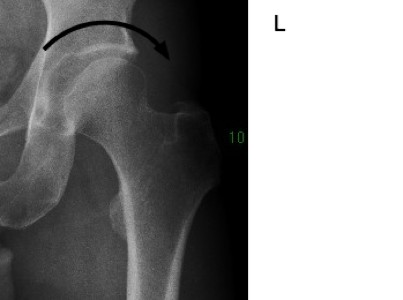

Mr P's relatively normal left hip.

Note the well rounded acetabulum and absence of an "unroofed" femoral head.

Interestingly, a small "pincer" defect. Any stiffness?